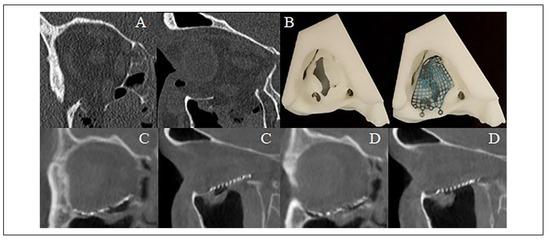

Figure 4.

(A) Coronal and (B) sagittal slices of the pre-operative computed tomography scan demonstrating an isolated right orbital floor blow-out fracture. (C) Coronal and (D) sagittal slices of the intraoperative O-arm “spin” demonstrating favorable position and contour of an “in-house” custom milled titanium mesh plate to reconstruct the orbit.